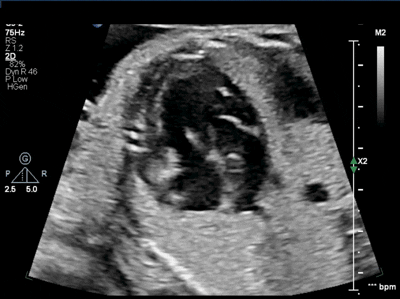

This sweep shows an easily missed defect by outside hospitals

What is DILV